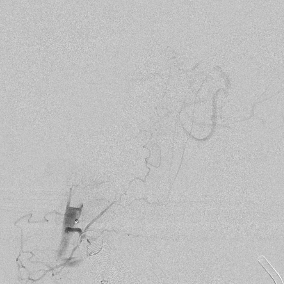

相逢就是缘,有求必全力以赴。立即进行全面评估,CTA和MRI发现颅内多发脑梗塞,脑干为重,双侧椎动脉颅内段基本看不到了,而进一步的DSA造影更为糟糕,左侧椎动脉的颅内颅外段直接全程完全闭塞,右侧颅外剩下一个小尾巴在血液中摇摇欲坠……,诺大的后循环仅仅靠纤细的后交通动脉从前循环借点血液过来,勉强续命,仅仅靠这点前循环的救急,可谓“杯水车薪”,不是“长久之计”,于是决定开通右侧闭塞的椎动脉(颅内+颅外,主要集中在V3+V4段)。

开通这么长节段的夹层所致的椎动脉,说说可以,做起来绝非易事,特别是颅内段,一旦跑到血管外出血,接近脑干,后果严重,谨慎开通的过程还算顺利,微导管带过就是磕磕绊绊不顺利,好吧,小球囊从上到下扩下来,不通,更换稍大球囊扩下来,还是不通,这夹层和狭窄不一样啊,支架导管带过仍然磕磕绊绊,不顺畅,铺开第一个支架,直接来了末端打开不良……,这么长的闭塞段,那得需要多少支架啊?万一放完了,钱花了,不通咋办?

微导管继续超过去,轻轻造影,开通的路径隐约返流闪现,立即改变策略,逆向铺路,开通成功。